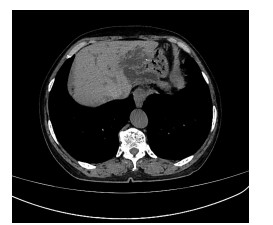

HIV infection with acute liver failure as the main manifestation: A case report

Fang YUAN, Jun SHI, Hailin TANG, Yiqun ZHOU, Fang XUE

2021, 37(7): 1670-1672. DOI: 10.3969/j.issn.1001-5256.2021.07.039

Abstract(762) HTML (328) PDF (2386KB)(28)

Abstract: